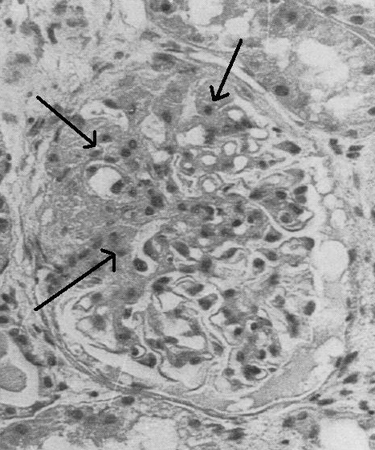

Light microscopy, immunofluorescence, and electron microscopy will reveal pattern of glomerular injury and severity.

[Figure caption and citation for the preceding image starts]: Light microscopy of kidney biopsy showing typical lesions of focal segmental glomerulosclerosis (arrows)Adapted from Nagi AH, Alexander F, Lannigan R. J Clin Pathol. 1971 Dec;24(9):846-50 [Citation ends].